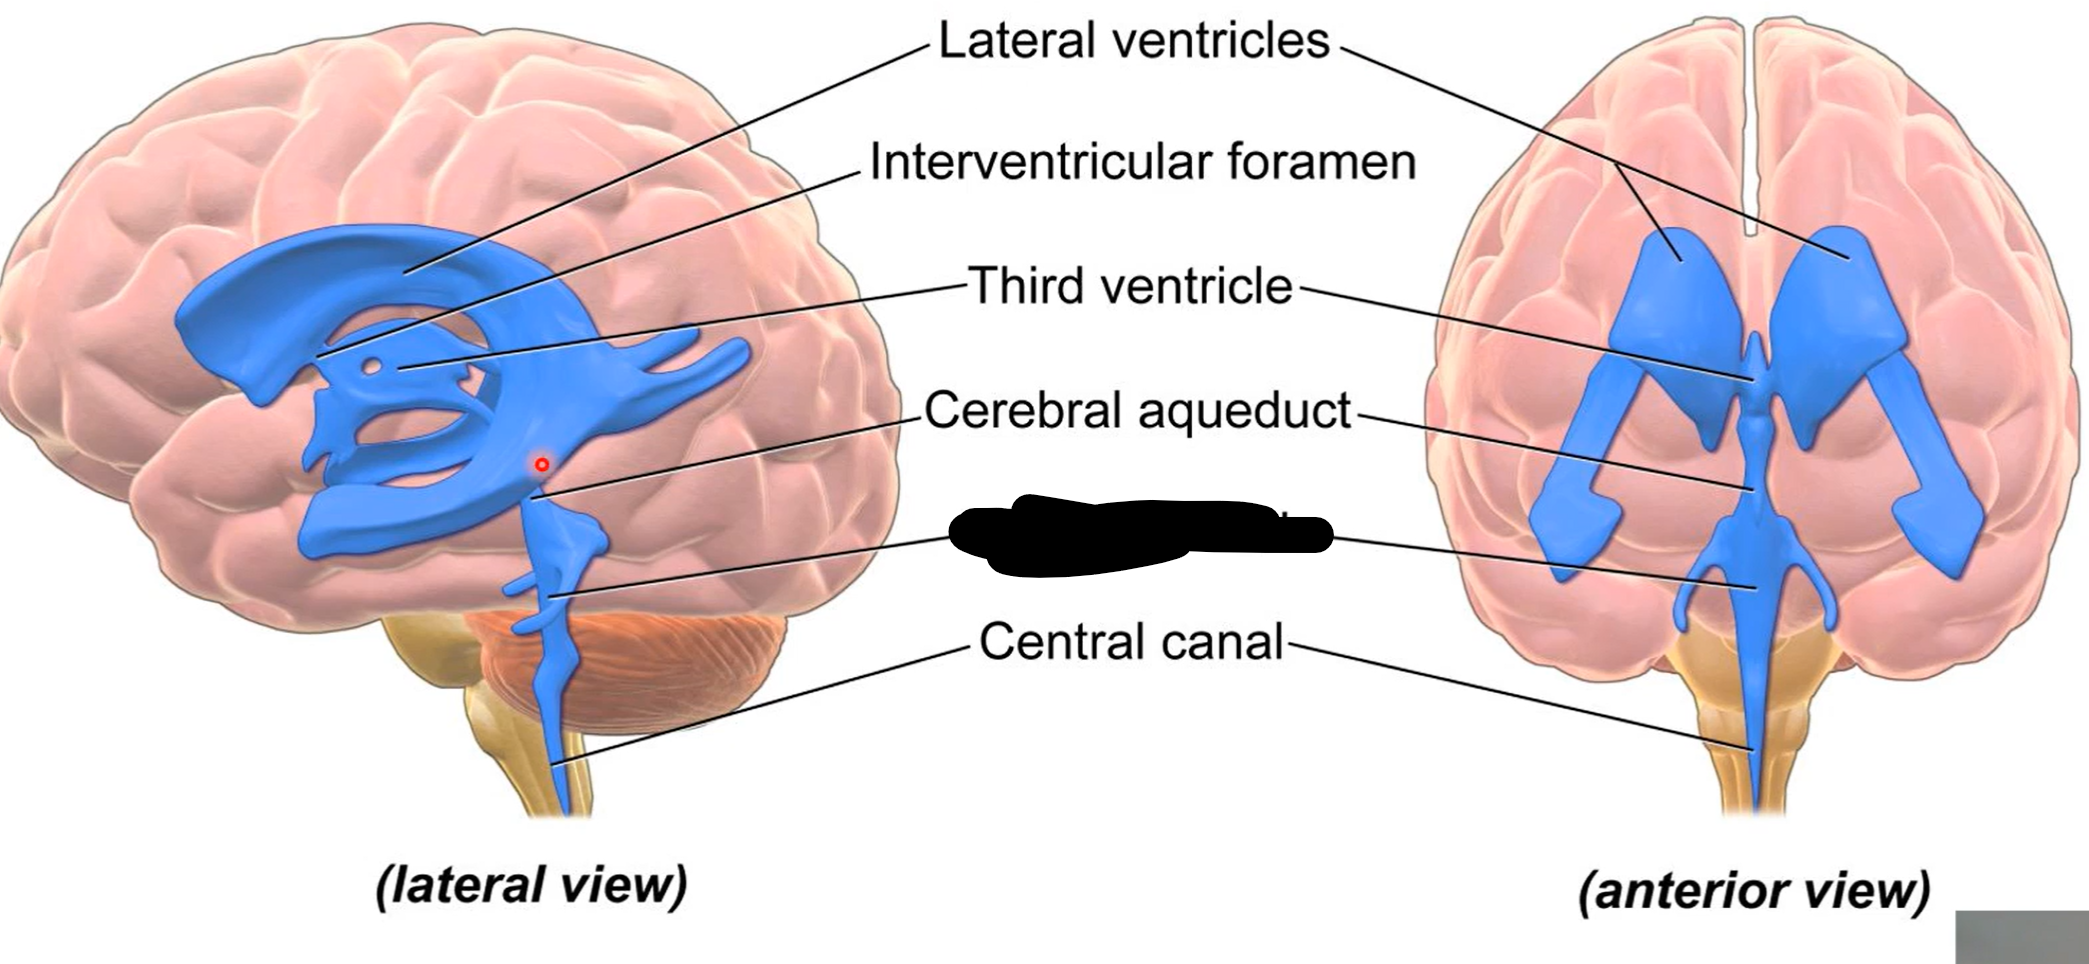

What do brain ventricles contain?

CSF

What makes CSF?

Choroid plexus

Where does CSF go from ventricles?

Subarachnoid space to enter circulation via arachnoid granulations

Choroid plexus

What carries CSF from 4th ventricle to subarachnoid space?

Median and lateral apertures

Arachnoid granulations

Lateral ventricles

Interventricular foramen

Third ventricle

Cerebral aqueduct

Fourth ventricle

Central canal